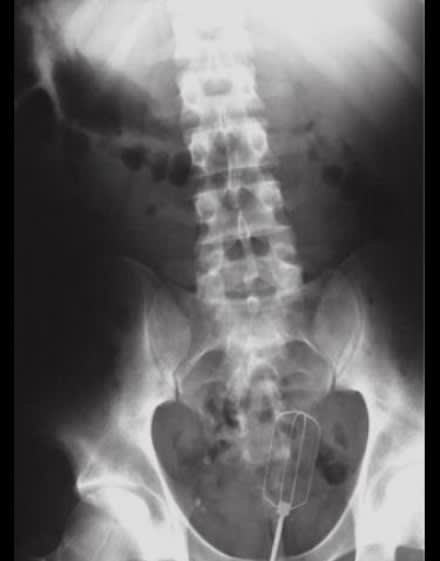

01/09/2017 à 11h09

Est ce que c'est du fake ? Paire de ciseaux

Img 0294 tifngb - Eugenol